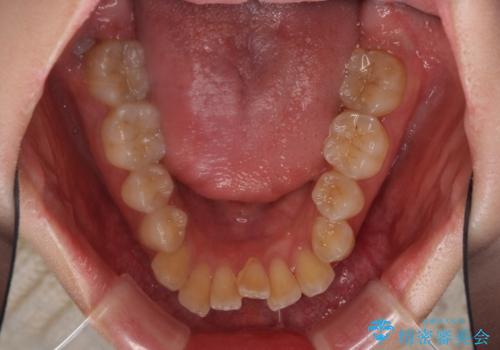

Eラインを改善したい ハーフリンガルによる抜歯矯正

- 口元の突出感を気にして来院された患者様です。

上下左右の第一小臼歯4本を抜歯して口元を下げる治療計画としました。

舌の突出癖が強く、口元を引っ込める力に拮抗してしまい、抜歯スペースを閉じるまでに時間がかかりました。

また途中出産もありましたが、無事に治療を終えることができました。